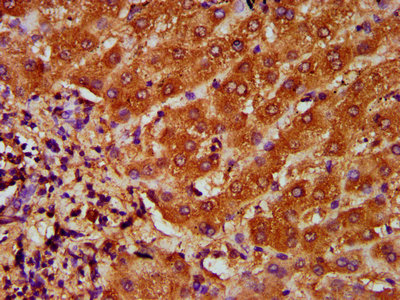

IHC image of CSB-PA14729A0Rb diluted at 1:200 and staining in paraffin-embedded human liver cancer performed on a Leica BondTM system. After dewaxing and hydration, antigen retrieval was mediated by high pressure in a citrate buffer (pH 6.0). Section was blocked with 10% normal goat serum 30min at RT. Then primary antibody (1% BSA) was incubated at 4°C overnight. The primary is detected by a biotinylated secondary antibody and visualized using an HRP conjugated SP system.

IHC image of CSB-PA14729A0Rb diluted at 1:200 and staining in paraffin-embedded human liver tissue performed on a Leica BondTM system. After dewaxing and hydration, antigen retrieval was mediated by high pressure in a citrate buffer (pH 6.0). Section was blocked with 10% normal goat serum 30min at RT. Then primary antibody (1% BSA) was incubated at 4°C overnight. The primary is detected by a biotinylated secondary antibody and visualized using an HRP conjugated SP system.